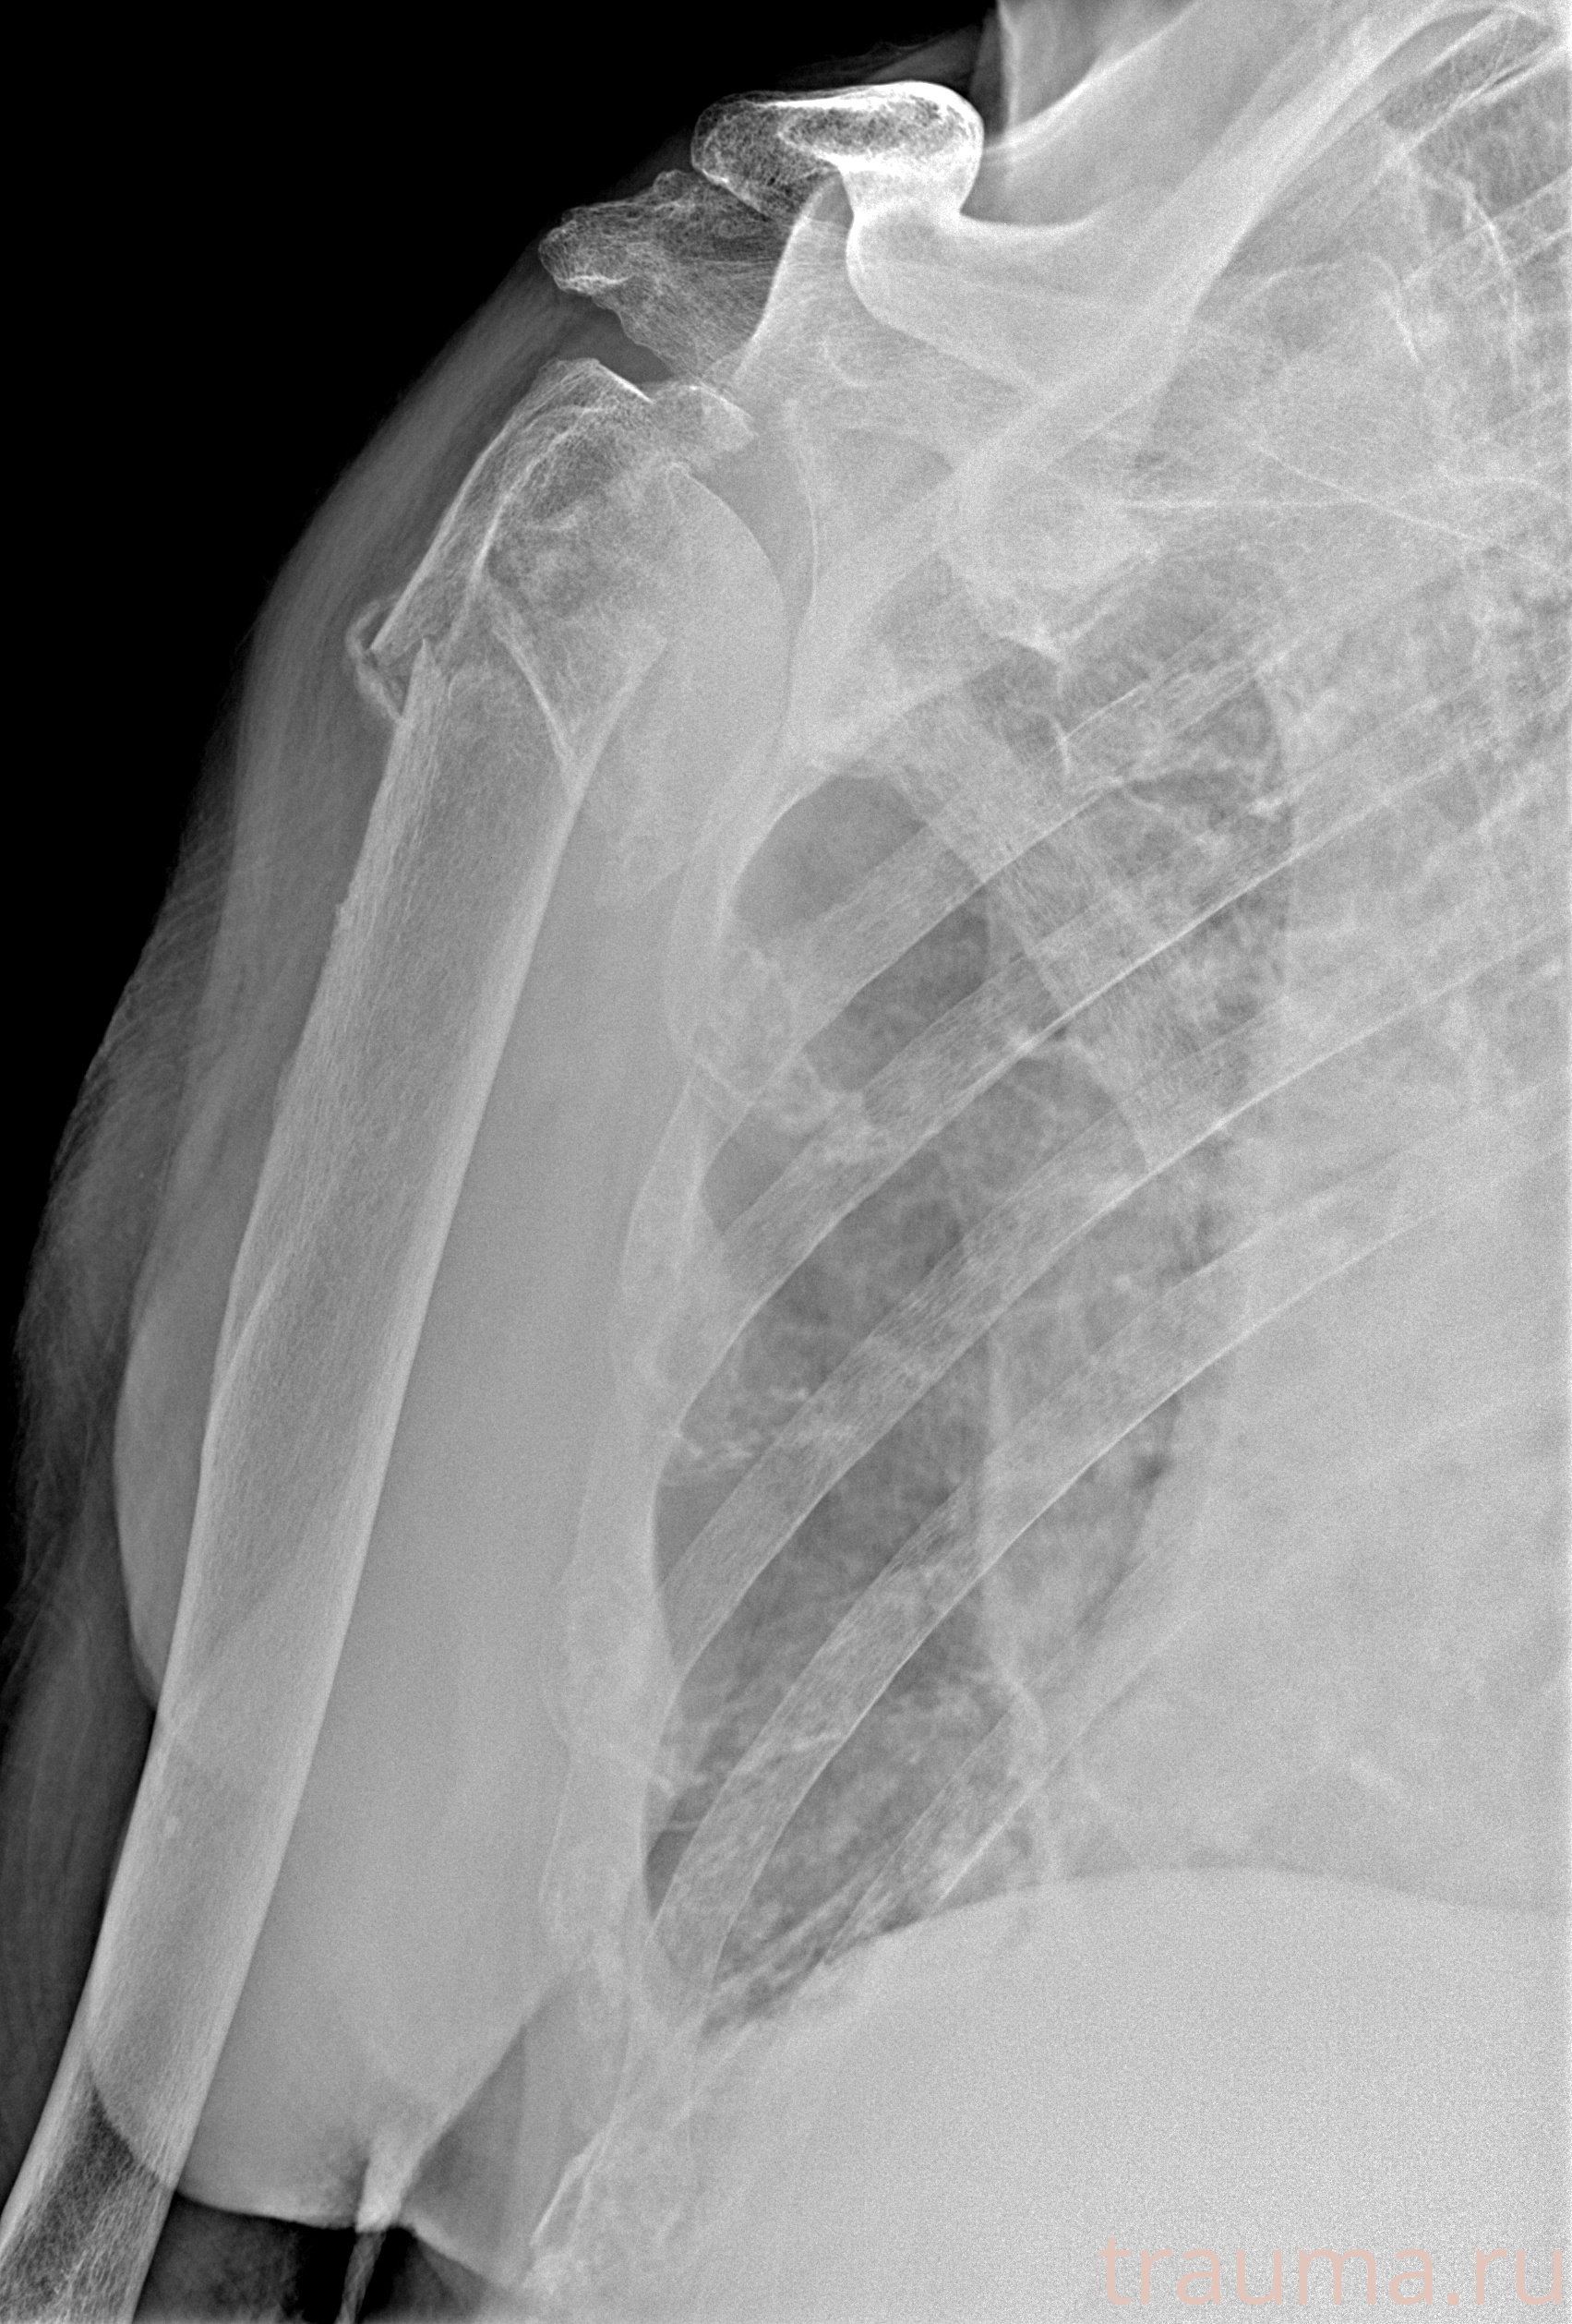

Рентгенограммы

Рентген на дому: по вашему адресу приезжает врач-рентгенолог, травматолог-ортопед с мобильным рентгеновским аппаратом, проводит диагностику травмы или заболевания, делает необходимые рентгенограммы, дает рекомендации по дальнейшему лечению. Получить качественные снимки в домашних условиях возможно благодаря уникальной методике, разработанной МосРентген Центром для института  Склифосовского